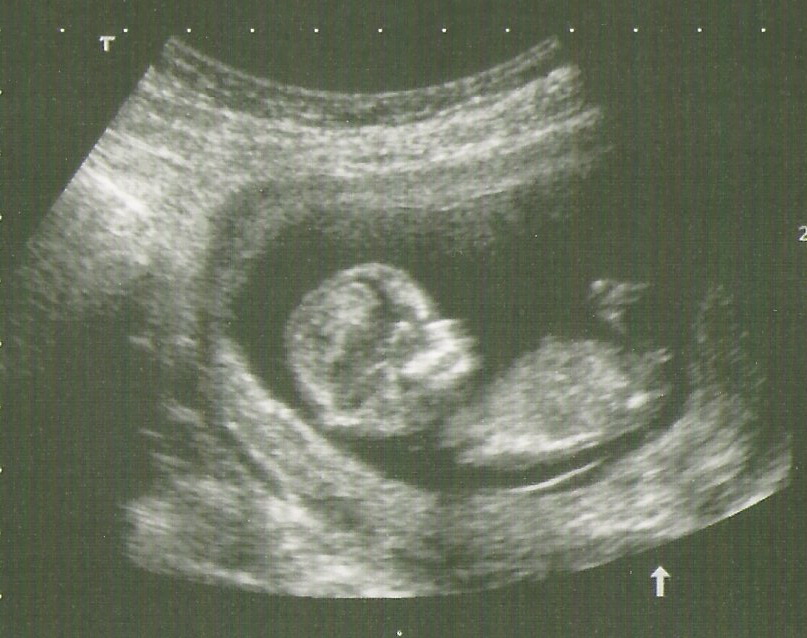

Hi ladies, just had my NT scan this morning and pretty sure I saw the nub during the U/S but not sure if this pic is a good shot. I can't decide for myself, so would love your opinions: boy or girl?